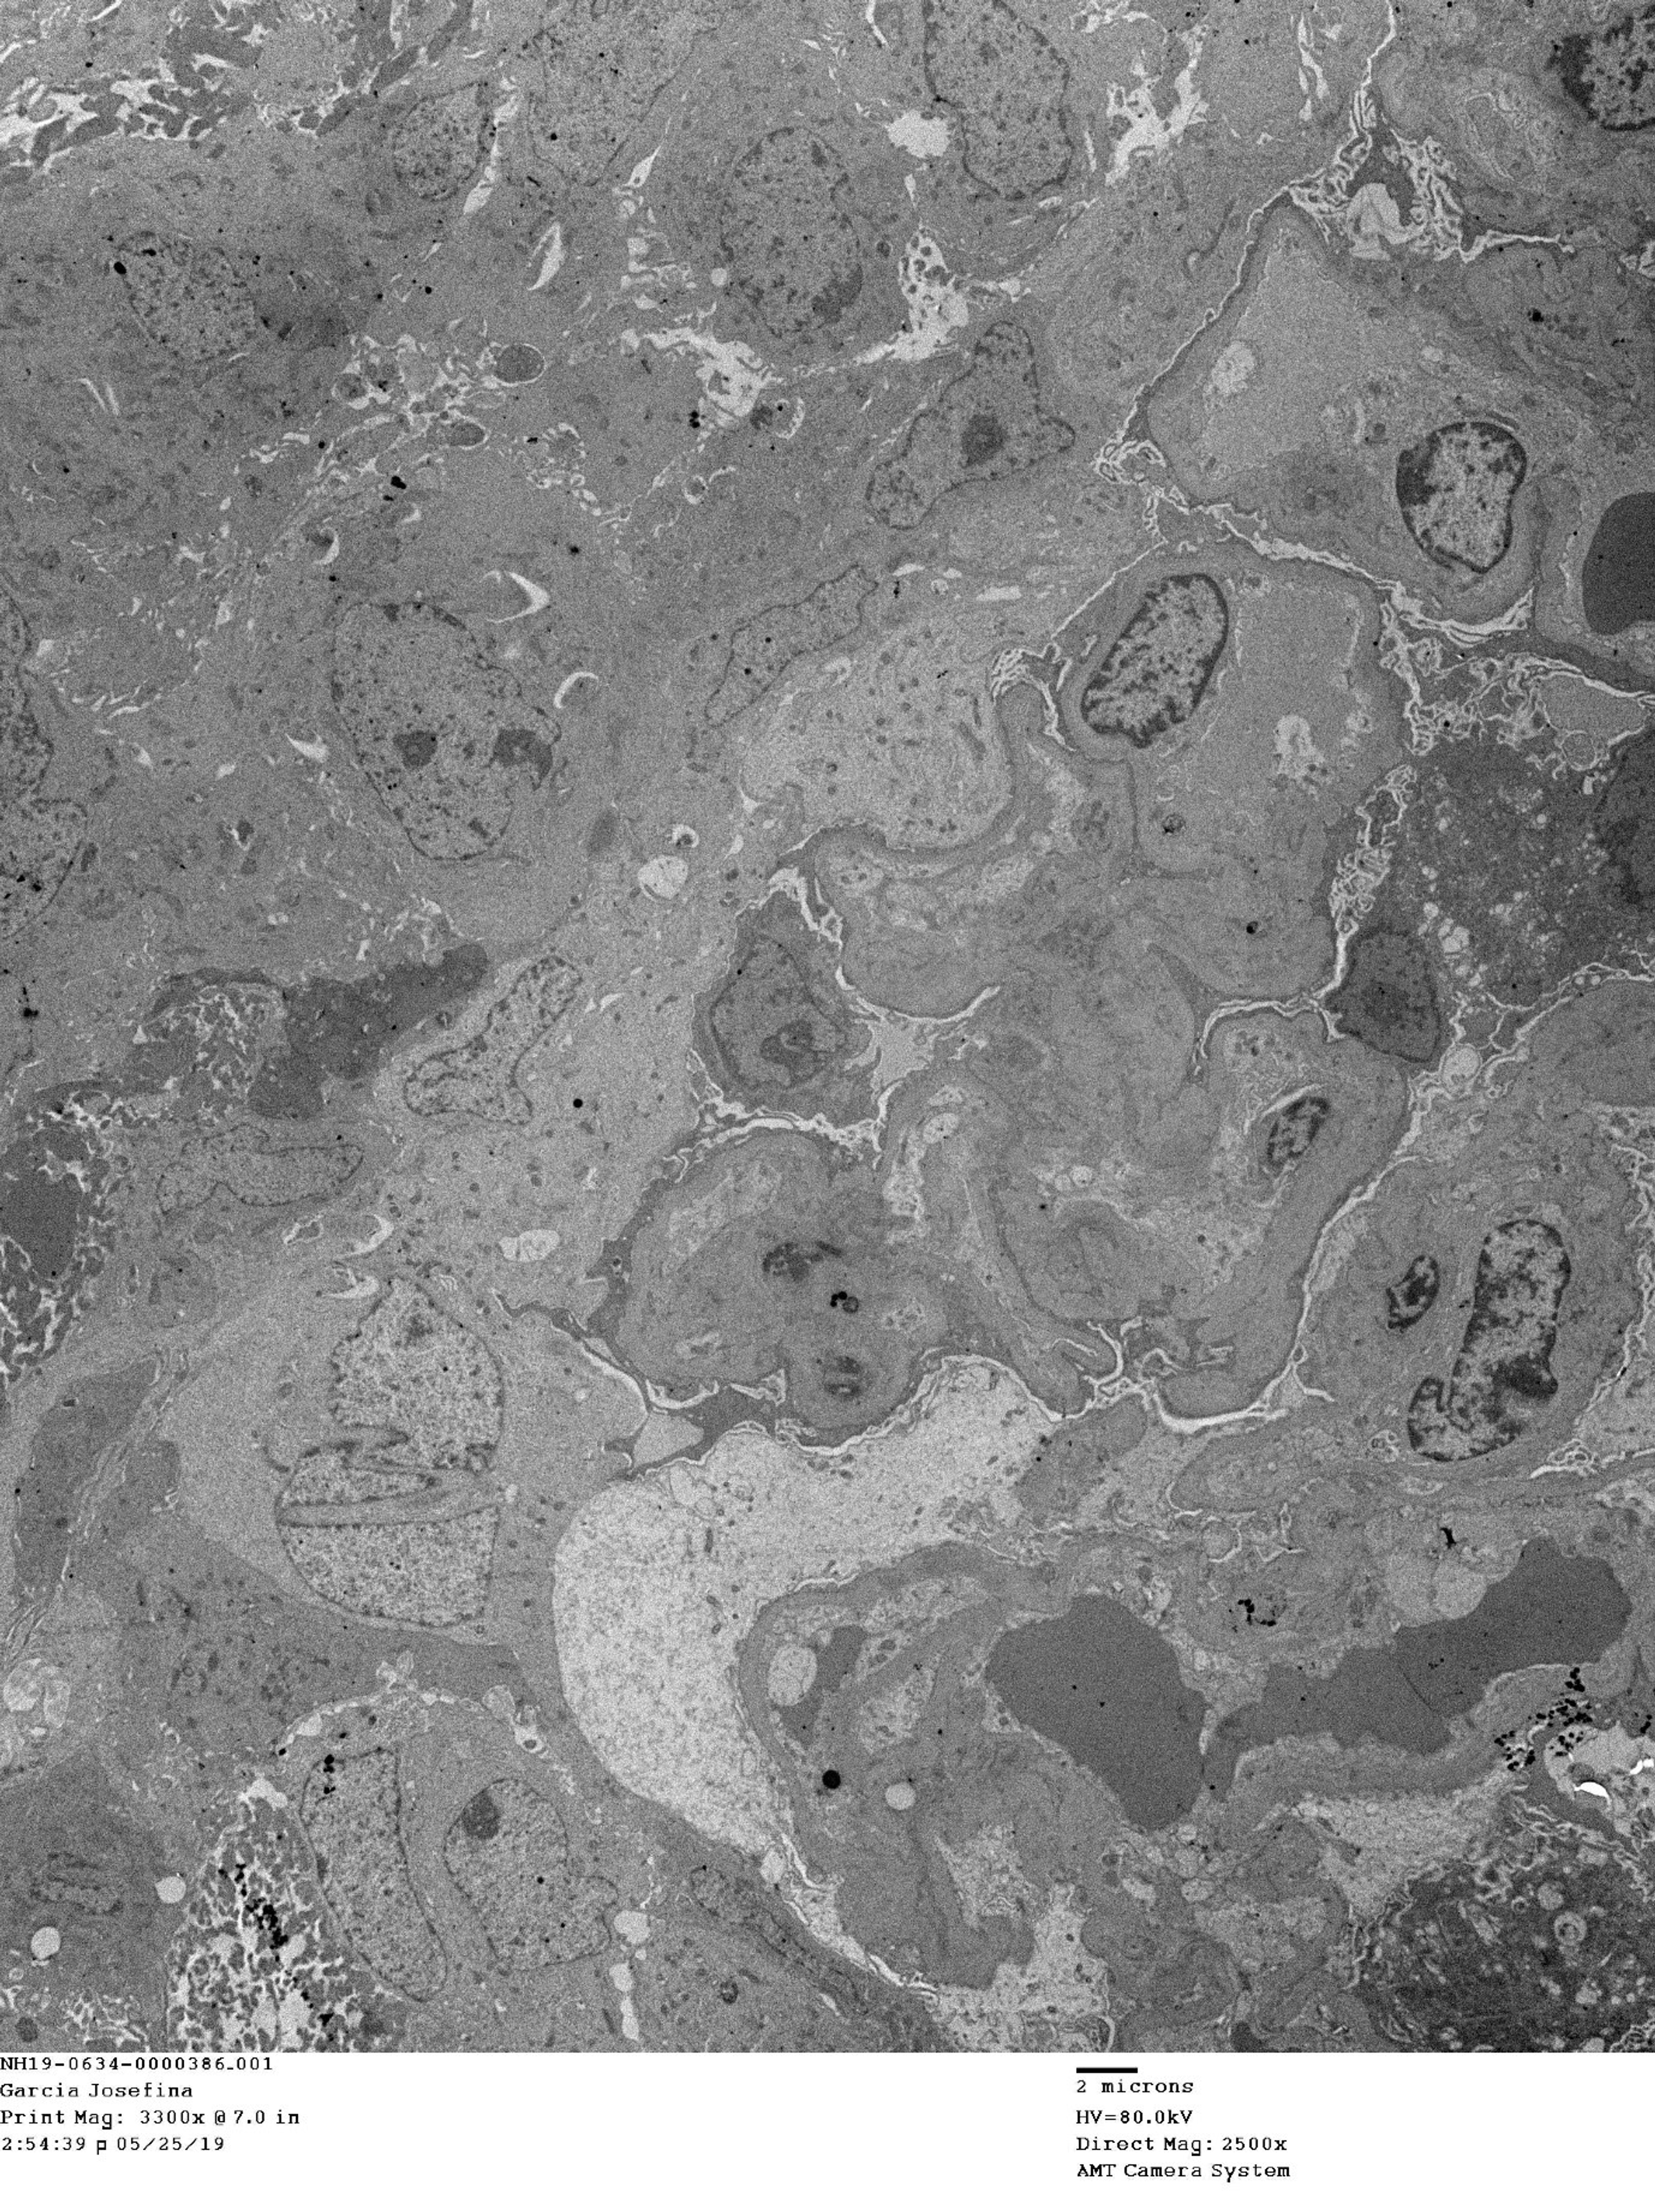

Spatial Transcriptomics-correlated Electron Microscopy | bioRxiv